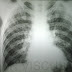

Rx de paciente donde se aprecia un infiltrado intersticial pulmonar difuso con eosinofilia (Síndrome de Loeffler). Obtenido de: http://quevihoy.blogspot.com/2011/02/blog-post.html

Síndrome de Loeffler, una forma de enfermedad pulmonar eosinofílica, descrita y explicada por Loeffler como infiltrados pulmonares transitorios y migratorios, que desencadena síntomas respiratorios, como por ejemplo: tos, expectoración, fiebre, y lo más relevante es eosinofílica periférica. Su causa podría enfocarse en Ascaris lumbricoides. Dicha enfermedad podría ser tratada con fármacos. Por último, gracias a los Rx tórax se observa opacidad pulmonar, o infiltrado intersticial difuso como forma de diagnóstico.